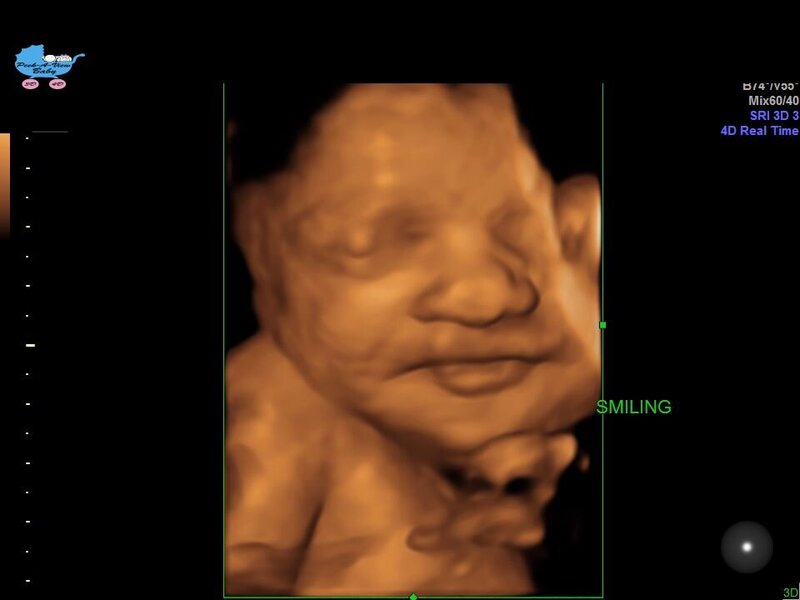

சிரித்துப் பழகுதல்

உங்களின் அபிமான சூப்பர் ஸ்டார் இந்த வாரம், உங்கள் 37 வார குழந்தை சிரிக்க நன்கு பயிற்சி எடுத்துக்கொள்கிறது. இப்போது, அவர்களின் புன்னகை சீரற்றது மற்றும் அவர்களின் உணர்ச்சிகளுடன் இணைக்கப்படவில்லை. ஆனால் அவர்கள் இரண்டு மாத வயதிற்குள், அவர்கள் விருப்பப்படி வேண்டுமென்றே புன்னகைக்க முடியும் (மற்றும் முகம் சுளிக்கிறார்கள்!). ஆனால் குழந்தைகள் அம்மாவின் கருவறையில் அழவும் செய்கிறார்கள். சில சமயம் அம்மா அழும்போது, கருப்பையில் உள்ள குழந்தை Feel பண்ணுகிறது. அதுவும் உணர்ந்து வருத்தம் கொள்கிறதாம்,என்னே இயற்கையின் விந்தையும் அம்மா–குழந்தை பிணைப்பும்.